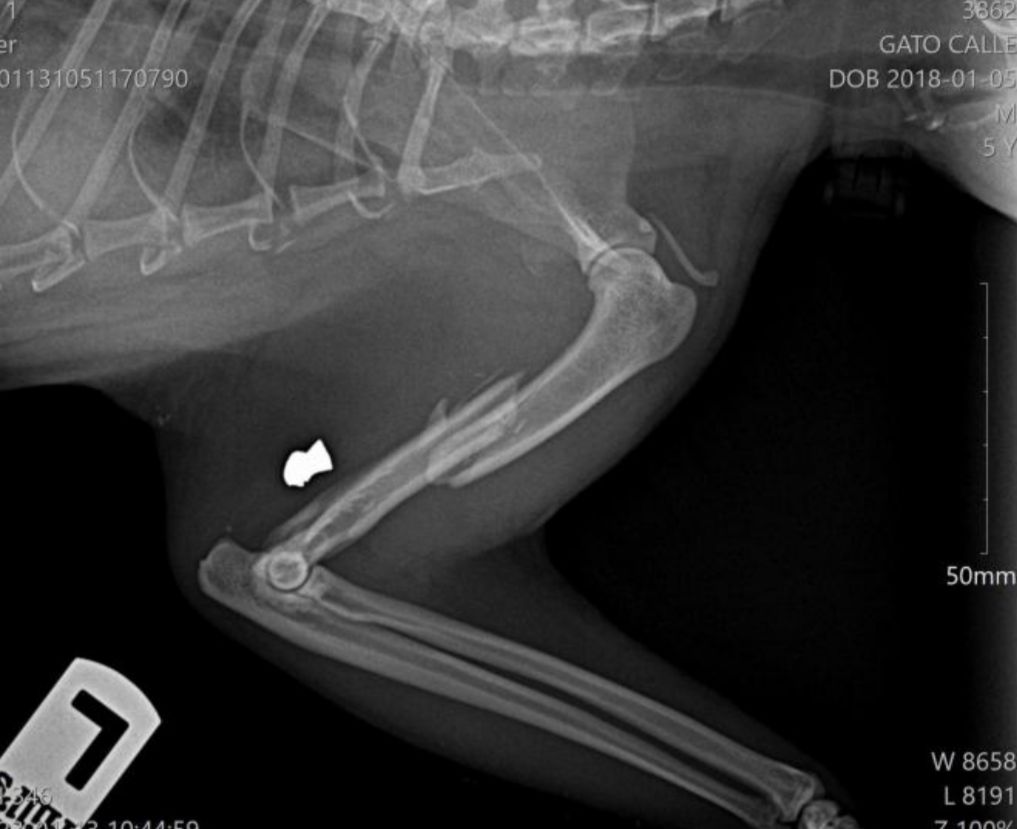

Las radiografías muestran un resultado totalmente inesperado e indignante. Lin tiene su pata totalmente destrozada por un disparo.

Lin permanece ahora recuperándose con analgesia y antibiótico a la espera de ver la evolución. Según indica el informe médico se trata de “fractura medial oblicua de húmero como consecuencia de disparo por arma de fuego con material alojado en la parte caudal del músculo tríceps braquial. Reducimos la fractura bajo anestesia general y la fijamos con aguja centromedular y placa bloqueada”

*Se aportan fotos del gato y radiografías de la pata.